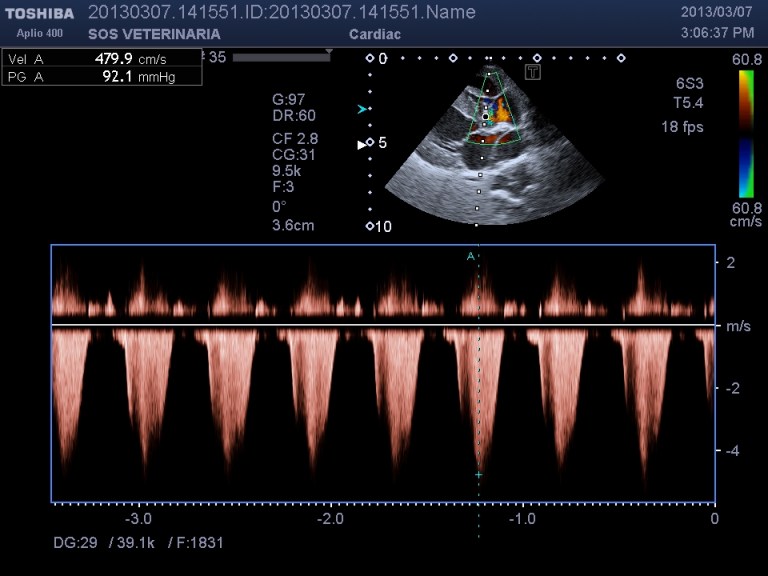

Ecco i filmati piu’ significativi osservare il flusso laminare che scorre parallelo alla parete laterale dell’arteria polmonare non piu’ continuo ma annullato in sistole dalla gittata in polmonare ,nel terzo filmato si vede l’ampolla del dotto